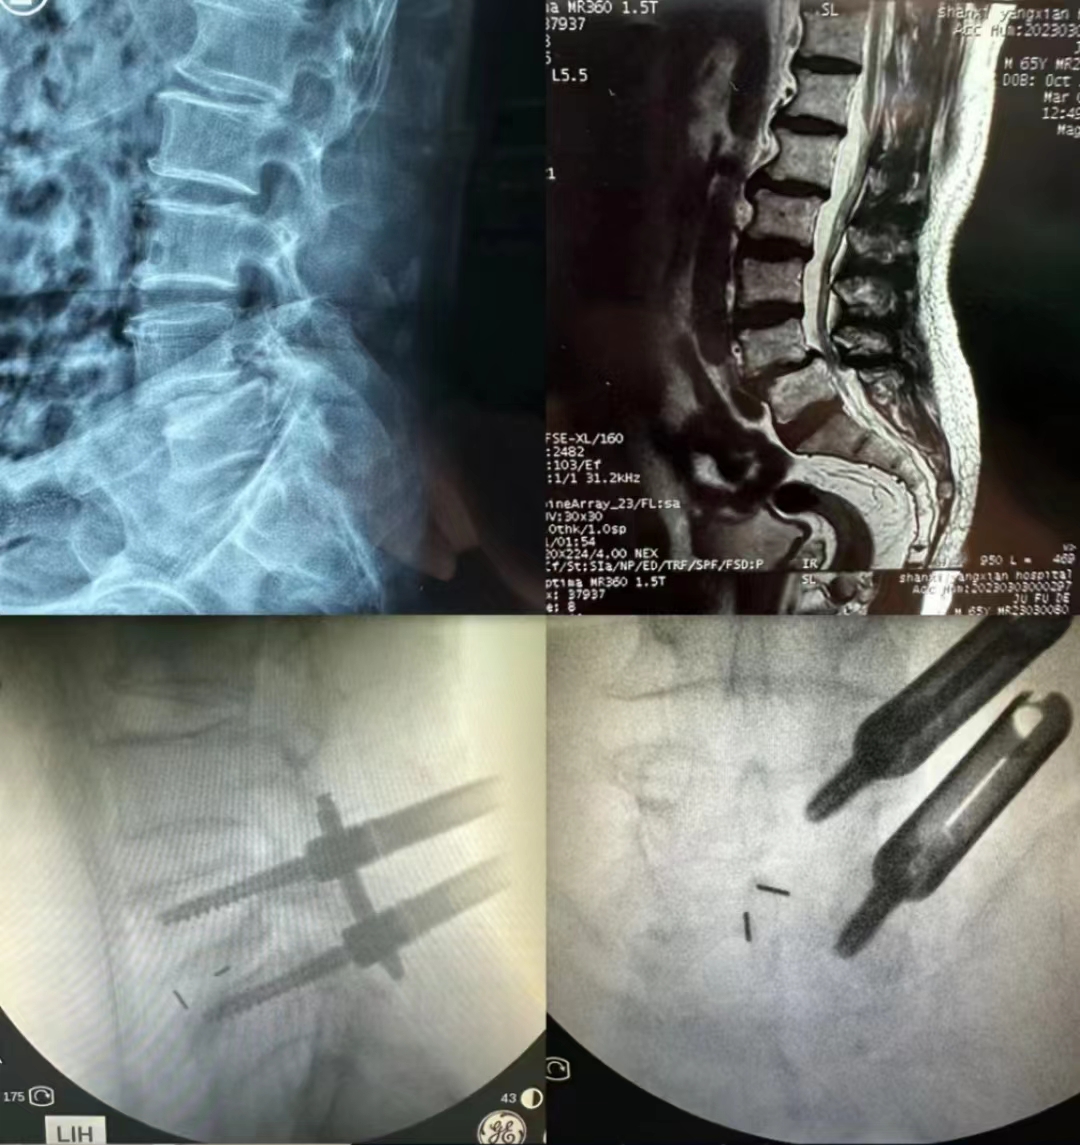

近日,我院对口支援医院——洋县人民医院骨一科在骨科中心-脊柱与骨肿瘤病区副主任蔡璇主持下,成功开展该院首例腰椎滑脱MIS-TLIF手术。

患者男,66岁。右小腿后侧疼痛1年半,平时走路只能走一段歇一段,对正常生活影响很大。洋县人民医院周伟医师接诊后,和刘颖主任、我院对口支援医师郭帅博士详细评估病情,发现该患者系腰椎滑脱合并椎管狭窄,具有手术指征,但患者提出能否采取微创手术的意愿。考虑到该院尚无开展腰椎滑脱MIS-TLIF手术的相关经验,遂联系到脊柱与骨肿瘤病区。经王栋主任安排,蔡璇副主任应邀主持协作团队针对患者病情进行了远程会诊讨论,设计出最佳手术方案,并制定了详细的术前、术中及术后风险情况应急预案。蔡璇副主任第二天上午在我院结束门诊工作后,便马不停蹄赶赴洋县,顾不上饮食和休息,一头扎进手术室。

虽然该术式在我院已是常规术式,但对于县医院而言并非易事,初次开展难度很大。术中蔡璇副主任向当地医生耐心讲解手术操作技巧,事无巨细、毫无保留。最终在周伟医师、郭帅博士配合下顺利完成手术,减压彻底,复位满意。术后患者疼痛消失,恢复良好,无并发症。无论患者还是当地医生对手术都非常满意,对我院专家更是称赞不已,期待进一步交流协作。

MIS-TLIF手术全称是微创经椎间孔腰椎间融合术(minimally invasive transforaminal lumbar interbody fusion),它通过肌间隙入路经椎间孔进行椎体间融合,避免了传统开放手术不必要的椎旁软组织剥离,减少了术中神经、硬膜牵拉。在减压融合固定安全可靠的同时具有创伤出血少、住院时间短、术后早期恢复日常工作生活的特点,是一种主流的腰椎微创融合手术方式。该手术的成功开展,标志着洋县人民医院对腰椎滑脱治疗又有了新突破,可以更好地为洋县及周边地区的患者提供更加优质的诊疗服务,对当地老百姓来说是一件意义非凡的大事。